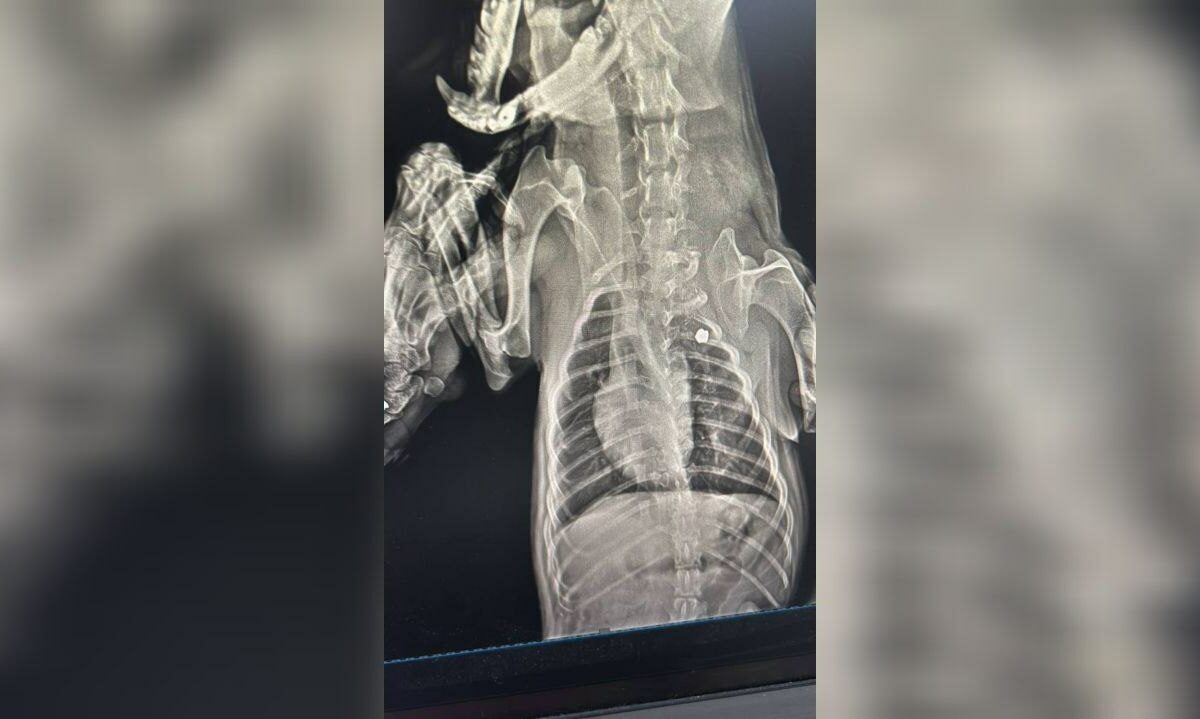

Фото t.me/pva_chp

О случившемся стало известно из публикации в местном паблике в соцсетях. По словам автора, местным жителям известно о двух случаях расстрела животных у одного дома. Они утверждают, что один и тот же мужчина на мотоцикле в первый раз выстрелил в собаку 2 августа. Пуля попала животному в грудную клетку и застряла там.